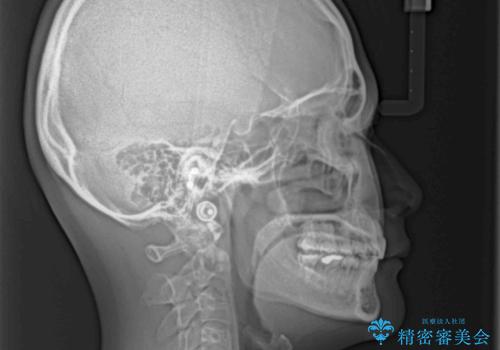

抜歯矯正により、口元の印象だけでなく、横顔の印象も大きく改善されました。